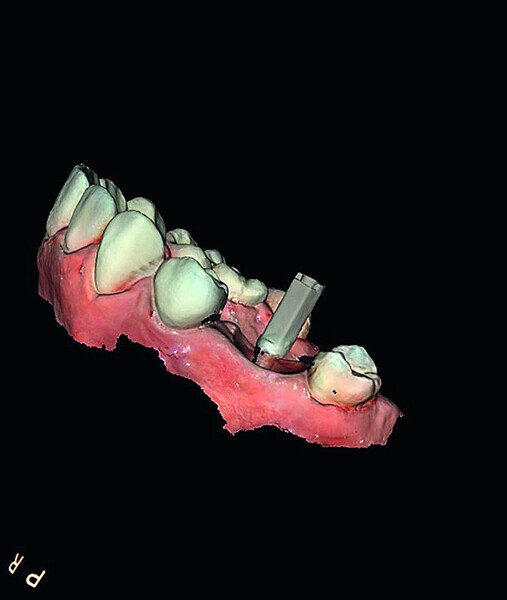

Digital workflow and application of PRF and ozone therapy in oral rehabilitation